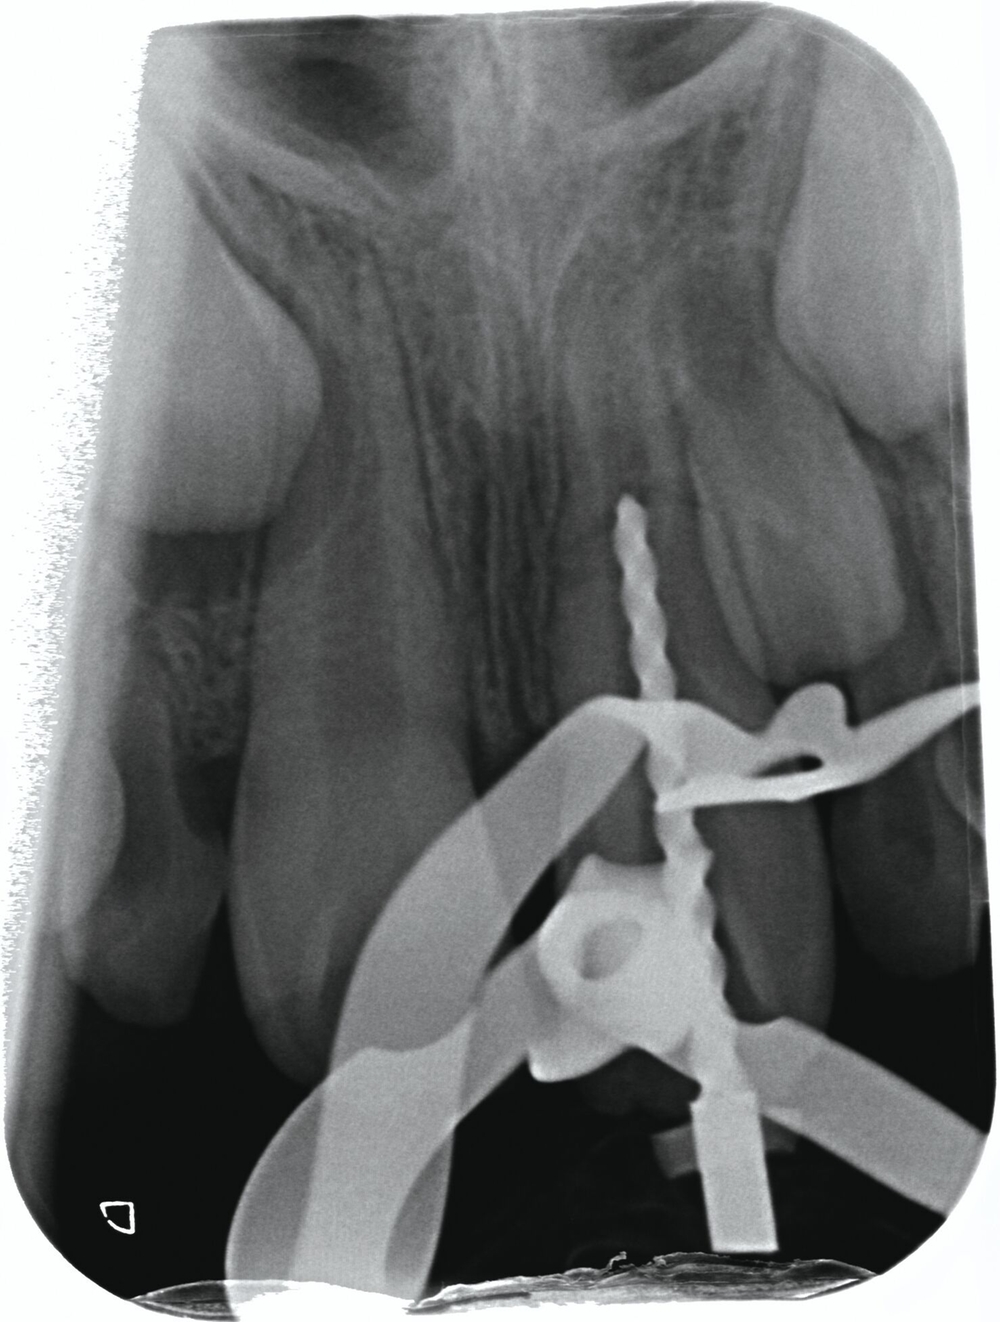

Zum Zeitpunkt des Beratungstermins lagen moderate, reizunabhängige Beschwerden sowie eine deutliche Perkussionsempfindlichkeit und keine Reaktion auf Kälte (— 40°C, Endo Coldspray, Henry Schein, Melville, USA) an Zahn 21 vor. Der horizontale Lockerungsgrad betrug I, die Sondierungstiefen lagen zirkulär bei 2 mm. Klinisch zeigte sich eine ausgeprägte Protrusion des Zahnes 21, die nach Schilderung der Eltern bereits vor dem Unfall vorgelegen hatte (Abbildung 1). Die Zähne 12, 11, 22 und 23 zeigten keine Auffälligkeiten und reagierten plausibel positiv auf Kälte. Zur weiteren Diagnostik wurden eine intraorale Aufnahme der Zähne 12-22 (Abbildung 2a) und eine Aufbissaufnahme (Abbildung 2b) der Frontzahnregion angefertigt. Auf beiden Röntgenbildern war deutlich eine Wurzelquerfraktur an Zahn 21 im mittleren Wurzeldrittel mit Dislokation zu sehen. Zusätzlich war im Vergleich zu Zahn 11 ein Unterschied im Wurzelreifungsgrad erkennbar. Auf Basis der röntgenologischen und der klinischen Befunde musste eine Pulpanekrose mit konsekutiver Entzündung des Parodontiums im Bereich des Bruchspalts als wahrscheinlich angenommen werden.

In der ersten Behandlungssitzung im August 2019 erfolgte unter Kofferdam und Lokalanästhesie ohne Adrenalin (Ultracain D, Sanofi, Paris, Frankreich) die Trepanation und mikroskopische intradentale Inspektion des Zahnes 21, bei der eine vollständige Pulpanekrose festgestellt werden konnte. Der Bruchspalt wurde röntgenologisch durch eine Kontrastaufnahme evaluiert (Abbildung 3). Gemäß dem Positionspapier der European Society of Endodontics für Revaskularisationstherapien erfolgte die Desinfektion des Endodonts mit 20 ml 3 % Natriumhypochlorit, anschließend eine Zwischenspülung mit 5 ml 0,9 % physiologischer Kochsalzlösung (NaCl, Braun, Melsungen, Deutschland) sowie eine Abschlussspülung mit 20 ml 17 % Ethylendiamintetraessigsäure (EDTA/CanalPro EDTA, Coltène, Altstätten, Schweiz). Nach der Trocknung des Kanals mit Papierspitzen wurde ein Calciumhydroxidpräparat (Ultracal XS, Ultradent, South Jordan, USA) in den Wurzelkanal eingebracht sowie mit einem sterilen Schaumstoffpellet und Komposit provisorisch verschlossen.